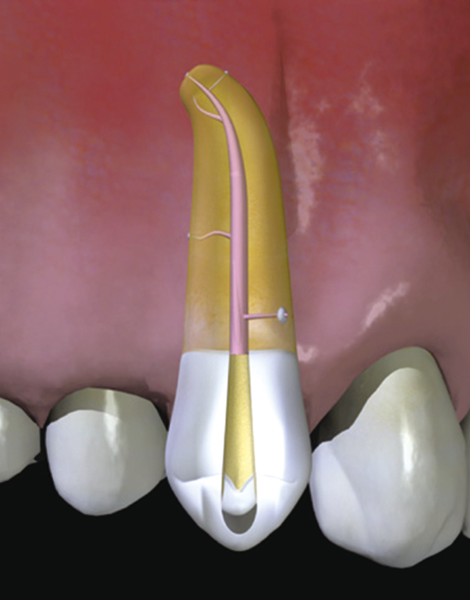

Inside the root of the tooth (the root of the tooth), there is a cavity called a "root canal" through which nerves and blood vessels pass. (Figure 15)

And just like a "tree," the tooth is lined with many root canals in an attempt to supply nutrients from the body. (Figure 16)

In other words, there is more than one nerve in the tooth.

It is inserting a wire-like instrument called a "file" into the root canal and scraping clean contaminated nerves and bacteria stuck in the root canal like a pipe cleaning. (Figure 17)

The inside is then rinsed clean and sealed tightly with a rubber-like material to keep the lid on the bacteria from entering the body. (Fig. 18)